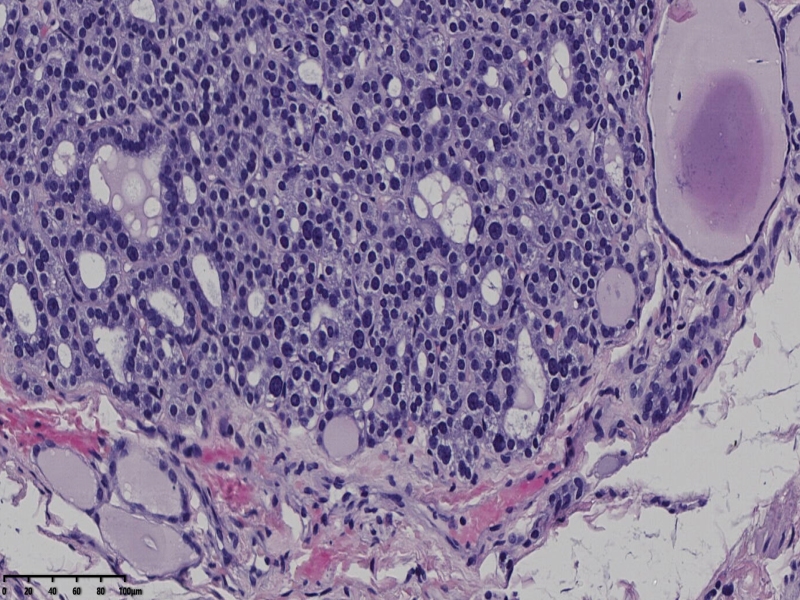

男、69、甲状腺左叶肿物,部分为囊性,囊内可见乳头状结构,上皮核重叠,没有核沟,没有毛玻璃样改变,没有核内假包涵体。255427

部分区域瘤组织与周围甲状腺组织分界明显,没有包膜样结构,滤泡结构为主,细胞异型明显。

会诊结果:(左叶甲状腺近峡部)甲状腺肿瘤,考虑为具有RAS核的乳头状癌,建议免疫组化及基因检测。

基因检测结果:良性。